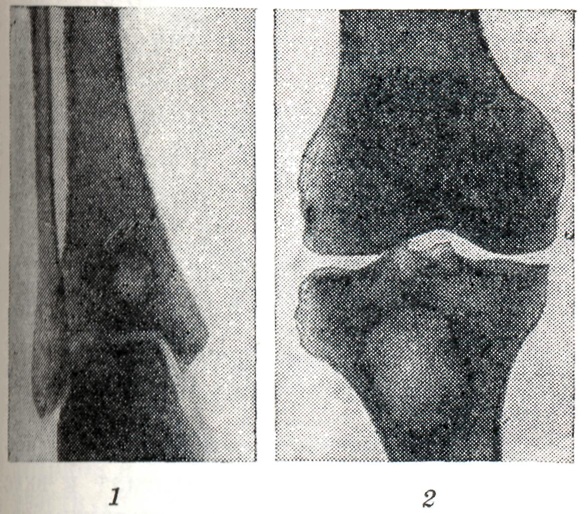

На рентгенограммах, Б. а. представляется в виде изолированной округлой или овальной полости в губчатом костном веществе метафиза или метаэпифиза (рис.,1 и 2) диаметром 2—3 см. Обычно расположен поверхностно под корковым слоем кости. Поражает чаще всего большеберцовую, реже бедренную и значительно реже плечевую, лучевую, локтевую и другие длинные трубчатые кости. Наибольший размер полости совпадает с длинником кости. В полости, как правило, не выявляется секвестров, внутренние контуры её ровные, вокруг неё вырисовывается узкая полоска склерозированного губчатого вещества, к-рая постепенно переходит в нормальную костную ткань.

Рис.

Абсцесс Броди (светлое пятно на рентгенограмме) в метаэпифизарных отделах болыпеберцовой кости: 1 — в дистальной части; 2 — в проксимальной части.